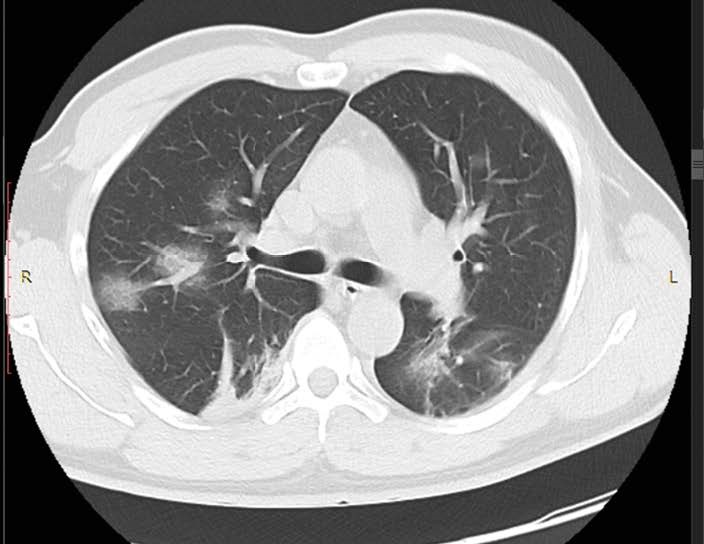

• the computed tomography system 64-slice manufactured by NIPK Electron Co. for primary assessment and differential diagnostics of chest diseases, as well as for revealing concomitant diseases. The modular CT unit can be equipped with a computed tomography system with another slice number as an option. According to the interim methodological guidelines “Prevention, Diagnostics, and Treatment of a new Coronavirus Infection” developed by the Ministry of Health of Russia, a CT scan is considered one of the basic methods of COVID-19 diagnosis.

The computed tomography system 64-slice (CT) installed in the module unit is equipped with a wide set of specialized software applications for diagnostic imaging in patients with respiratory disorders, vascular abnormalities, cancer, as well as for assessment of cerebral, renal, and hepatic blood supply. Thanks to this, CT is in high demand not only during the COVID-19 pandemic.